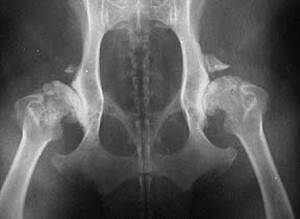

- в запущенных случаях у взрослых собак – потеря опороспособности конечности, развитие артрозов.

Основное проявление дисплазии – болезненность, кроме хромоты, это может проявляться как частый отдых при прогулках, отказ подниматься по лестнице (боязливое отношение к лестницам). Болевой синдром обычно не связан непосредственно с дисплазией, его вызывает остеоартроз, развивающийся на фоне отклонения в развитии, либо вызванные этими же причинами разрушения в суставе (истирание гиалиновой прослойки, нарушение целостности капсулы, и тд). Также даже легкие степени дисплазии увеличивают вероятность получения ряда травм, например, вывих тбс, разрыв передней крестовидной связки, и тд.

Для серьезный дегенеративных нарушений в работе сустава, вызывающих артроз, сильную болезненность и потерю опороспособности конечности, необходимо оперативное лечение. После проведения тщательного обследования, в зависимости от причины дисплазии, строения, породы, веса, возраста и состояния здоровья собаки выбирается наиболее эффективный хирургический метод. Наиболее популярные методики: резекция головки бедра, денервация капсулы сустава, миоэктомия, остеотомия таза, протезирование сустава и тд.